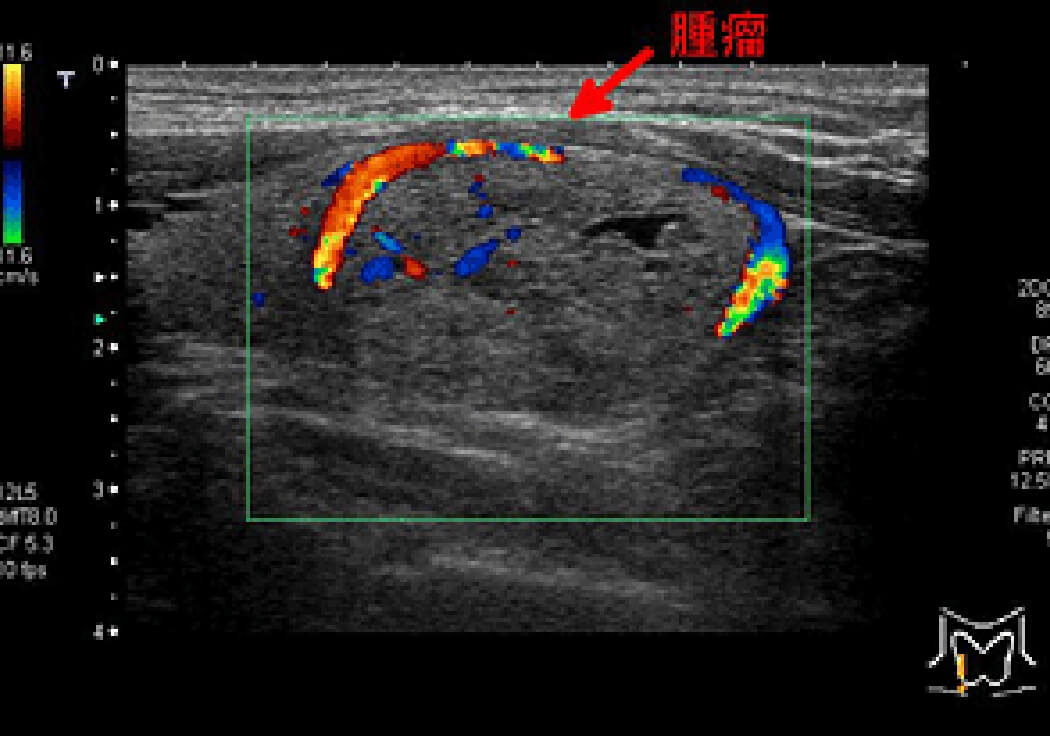

甲状腺超音波(頚動脈エコー)

甲状腺の異常を調べる検査です。甲状腺の腫大や萎縮、腫瘤の有無などを調べます。襟元が開いた状態で、ベッドに仰向けになって検査します。

腹部超音波検査同様にゼリーを塗り、探触子(プローブ)を頚部(首)にあて、甲状腺の断面層の画像をモニターで観察します。

甲状腺腫瘤の例